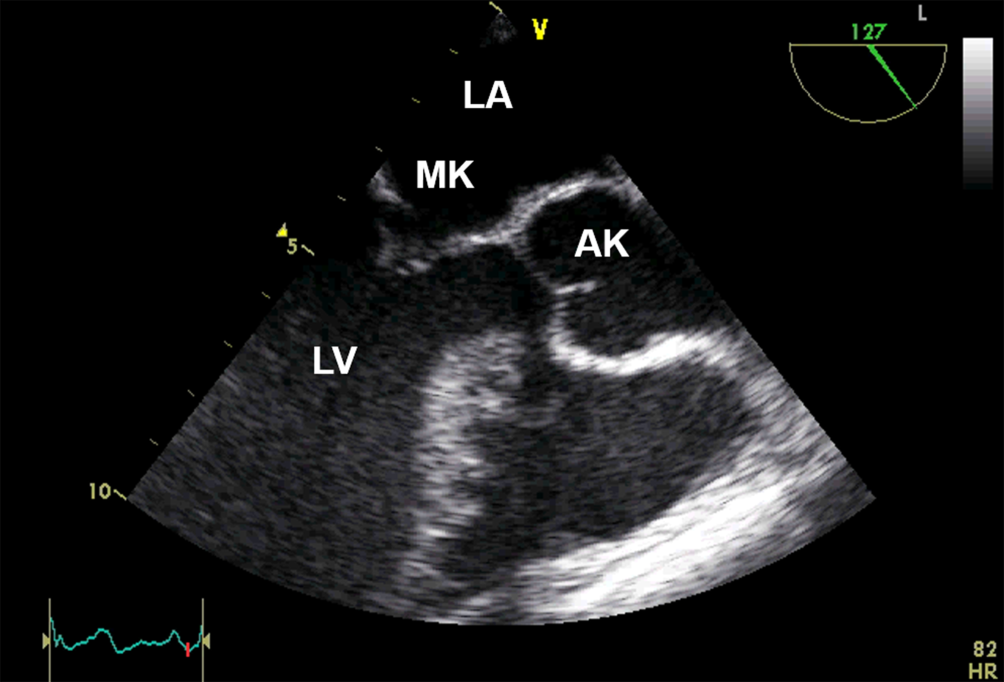

Anlotebene: lange Achse

Sondenposition: mittösophageal

Rotationswinkel: 130°